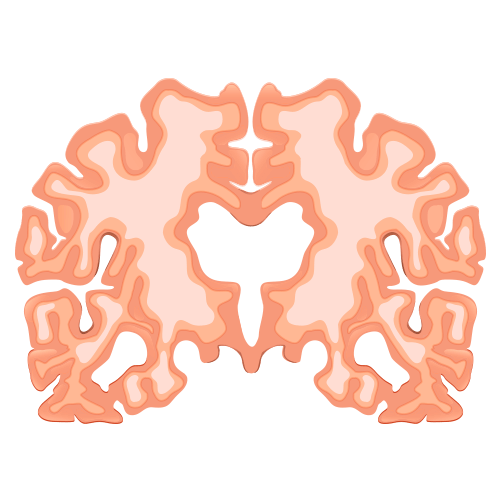

Impacto do Alzheimer no cérebro saudável